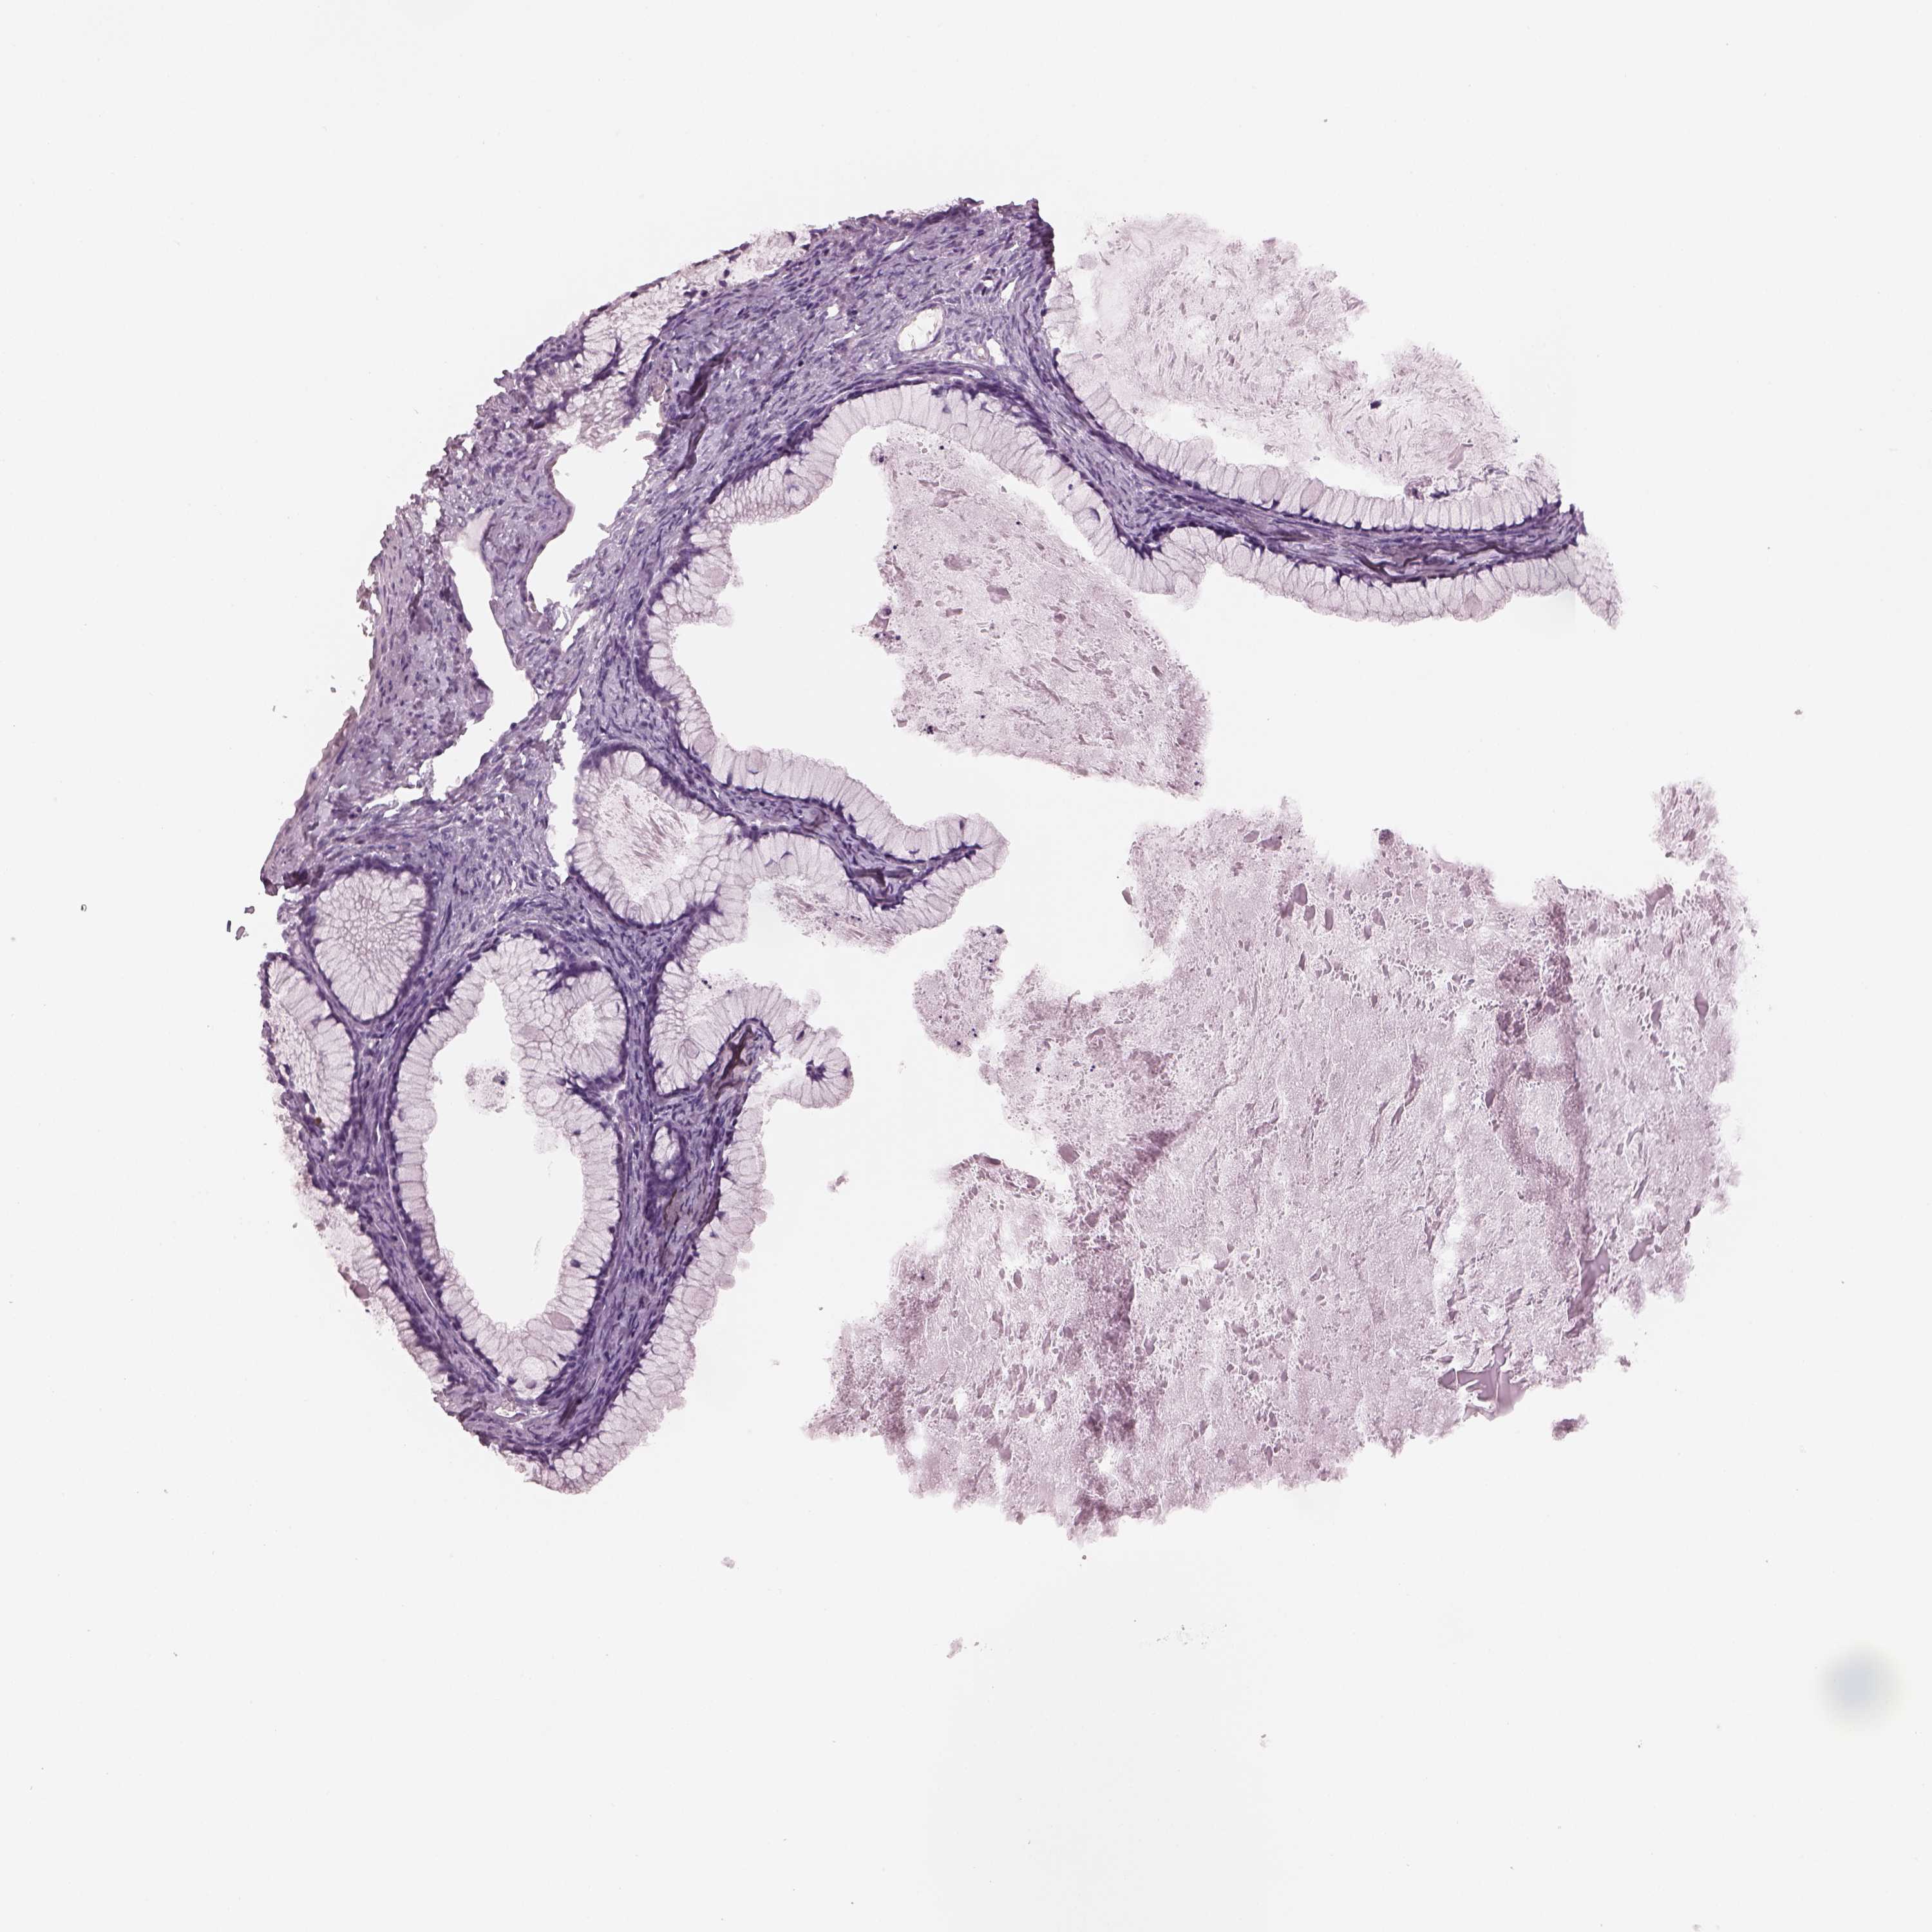

OVARIAN CANCER - Protein expressioni

A mouse-over function shows sample information and annotation data. Click on an image to view it in a full screen mode. Samples can be filtered based on level of antibody staining by selecting one or several of the following categories: high, medium, low and not detected. The assay and annotation is described here.

Note that samples used for immunohistochemistry by the Human Protein Atlas do not correspond to samples in the TCGA dataset.

Antibody stainingi

Antibody staining in the annotated cell types in the current human tissue is reported as not detected, low, medium, or high, based on conventional immunohistochemistry profiling in selected tissues. This score is based on the combination of the staining intensity and fraction of stained cells.

Each image is clickable and will lead to virtual microscopy that enables deeper exploration of all samples and also displays staining intensity scores, fraction scores and subcellular localization as well as patient and tissue information for each sample.

Antibody HPA070355

Antibody HPA078303

Cystadenocarcinoma, serous, NOS

Cystadenocarcinoma, mucinous, NOS

Carcinoma, endometroid